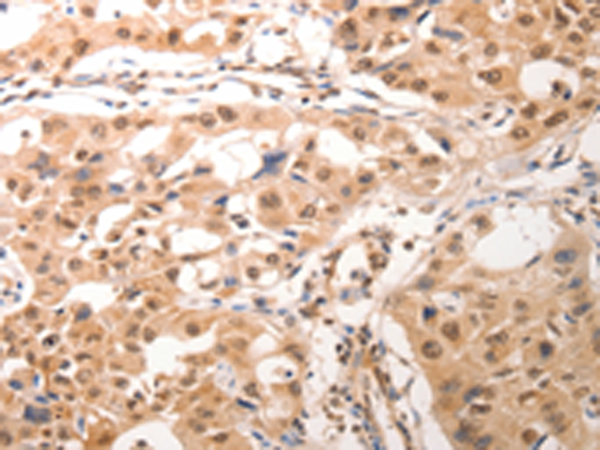

分类: 科研抗体货号: P10723别名: KGF; HBGF-7应用: IHC反应种属: Human, Mouse, Rat